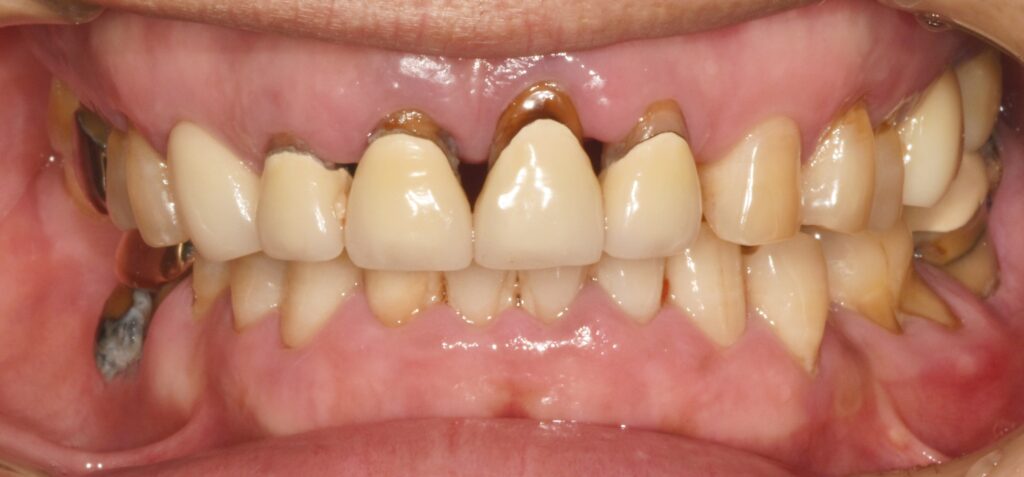

60대 남성분께서 치아 전체가 아프다며 치과에 내원하셨습니다.

상태는 아래와 같았어요.

어금니뿐 아니라 앞니 쪽에도 심한 치주 질환으로(잇몸질환) 치아가 많이 흔들리고 부어 있었습니다.

어금니는 아파서 씹지를 못하고 앞니는 흔들리기도 하지만 심미적으로도 안 좋아서 일상생활이 힘드신 상태였습니다.